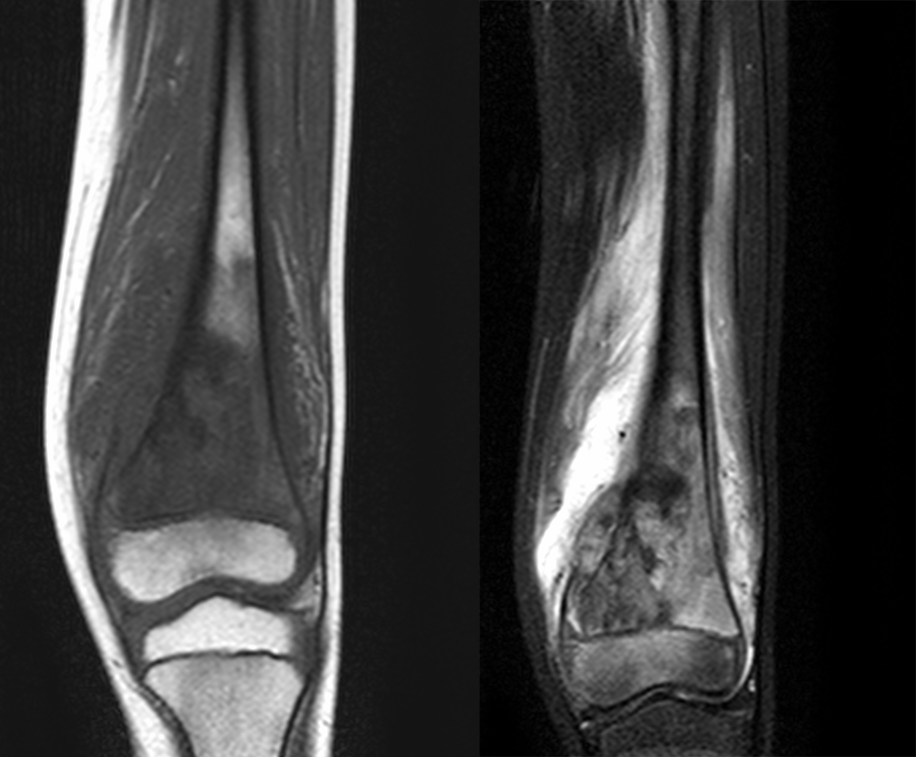

瘤周水肿

肿瘤周边的骨髓水肿表现为 T1WT 低信号和 T2WI、STIR 高信号边界模糊的片状影,软组织肿块邻近的正常软组织成分,尤其是肌肉内亦可出现水肿,表现为肿块周围沿肌束方向分布的边界模糊的片状或羽毛状影,有时可连成片。瘤周水肿常见于恶性肿瘤(图 58),但也可见于某些良性肿瘤如软骨母细胞瘤(图 59)、骨样骨瘤和骨嗜酸性肉芽肿(图 60)等。

图 58.瘤周水肿:骨肉瘤

图 59.瘤周水肿:软骨母细胞瘤